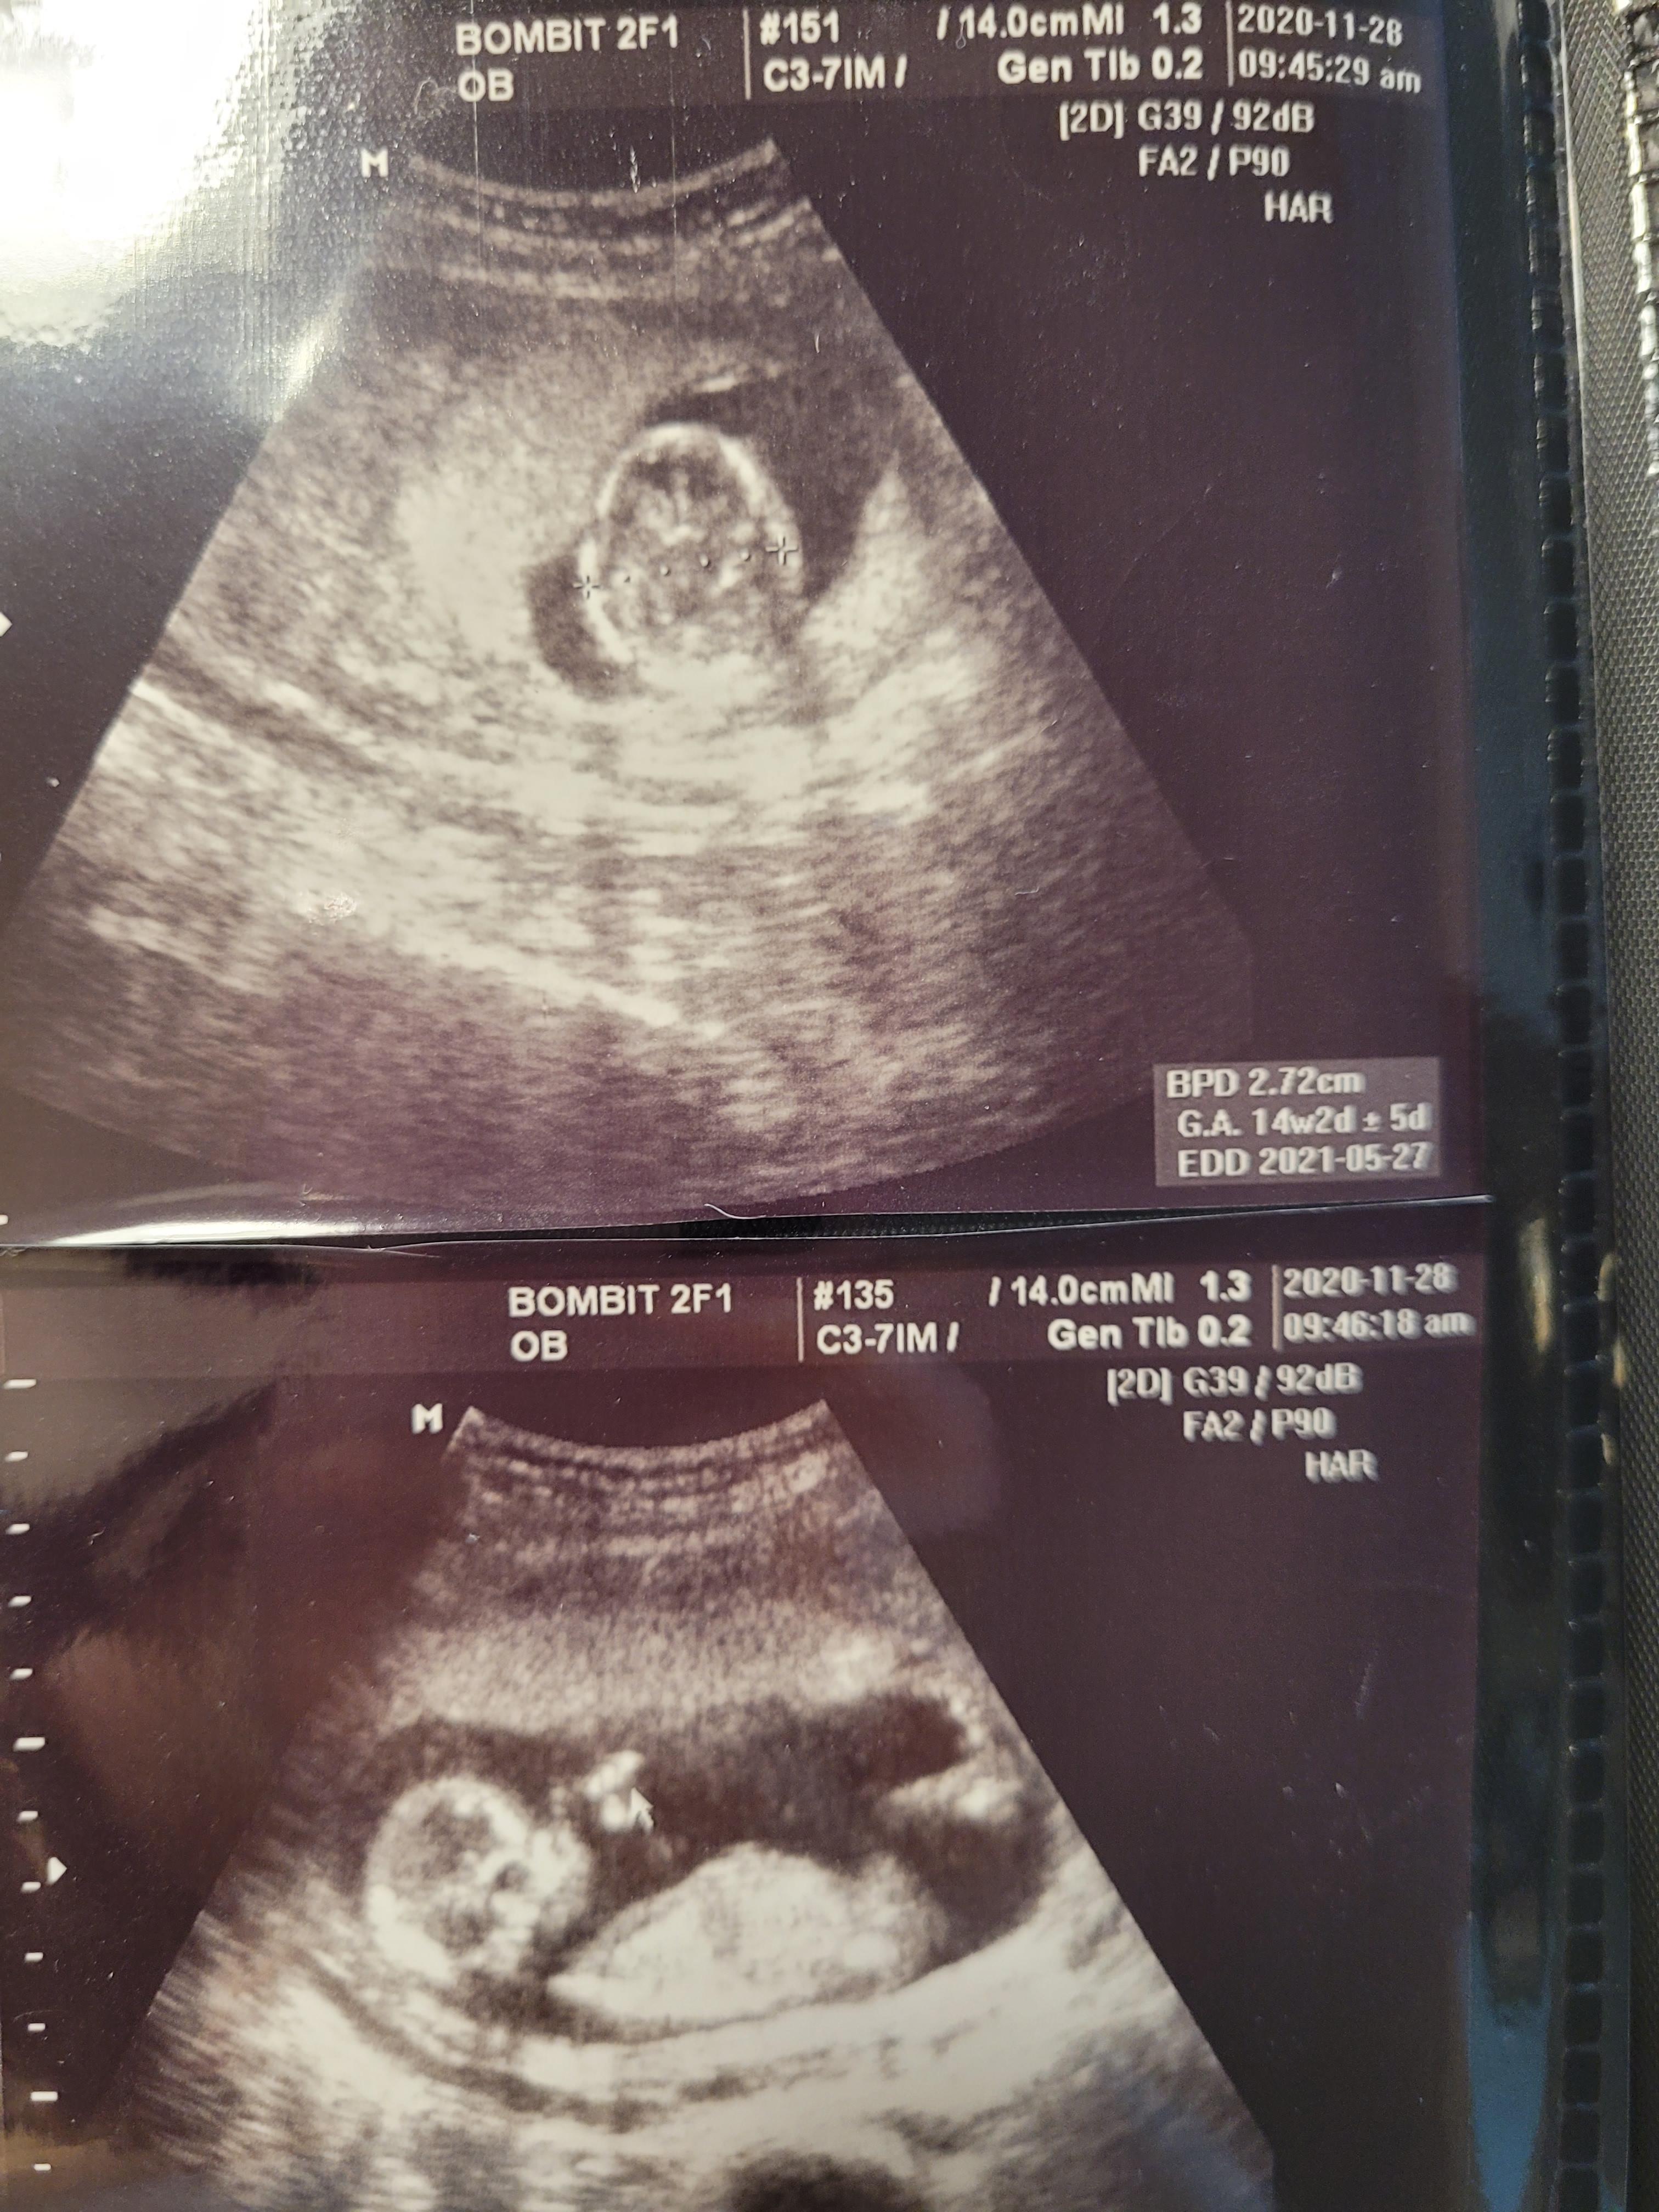

먼저 초음파를 보기로했고요.

걱정과 달리, 행복이는 아주 잘 자라고 있었어요.

아무 문제도 없었고요.

입덧이 끝나서인지 원래 주수에 맞게 잘 자라고있었는데 이제 더더더 잘 크고있네요.

주수보다 1주일이상 큰 상태였고, 이때부터 쭉 원장님도 아가가 발육이 좋다고 늘 칭찬해주셨어요.

이번 초음파를 보시더니 다리 사이에 무언가가 너무나 잘 보인다고 하시며

사진으로 캡쳐도 해주시고요ㅎㅎ

그렇게 저는 아들맘이 되었어요^^